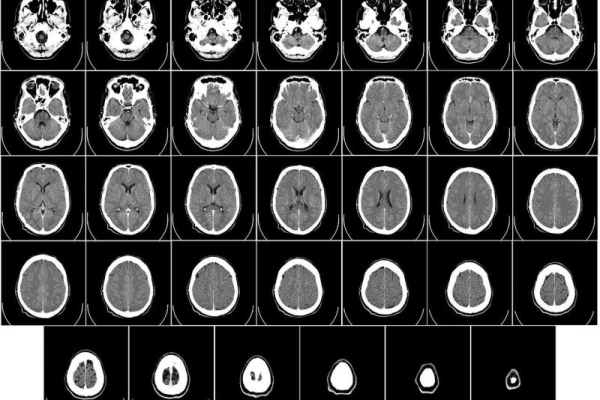

MRI brain scans of all six patients enrolled in the trial showed rapid tumor reductions occurring within a day or two of treatment.

The strategy seemed to work: MRI scans taken just 24 and 48 hours after CAR T delivery showed a remarkable shrinkage of tumors.